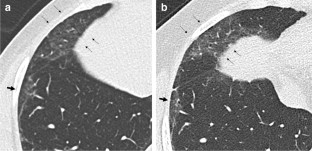

Fig. 2